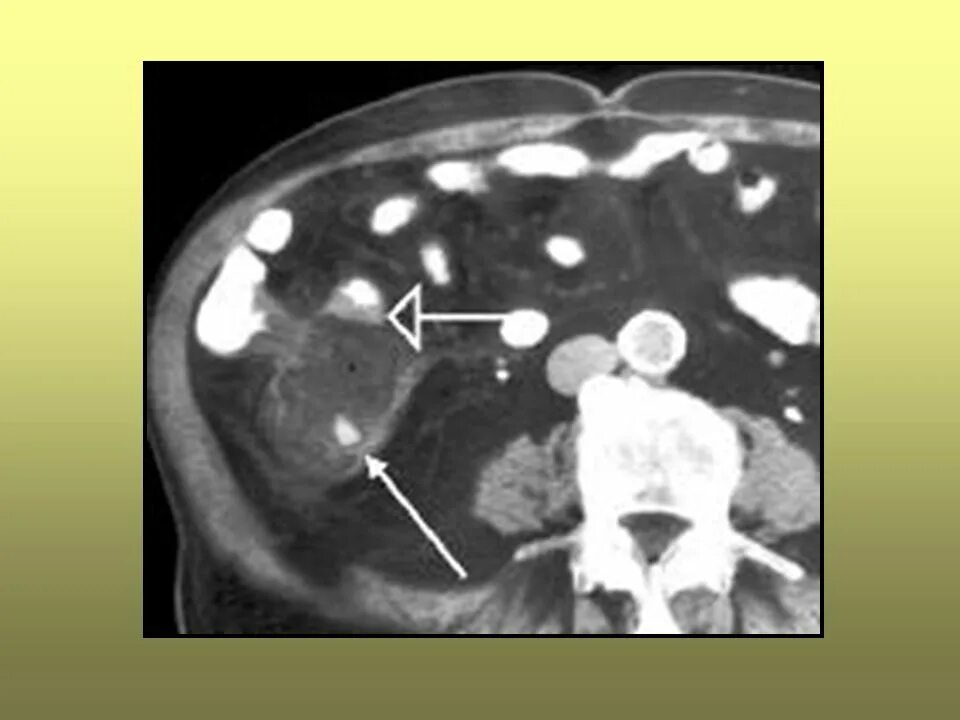

Абсцесс при аппендиците